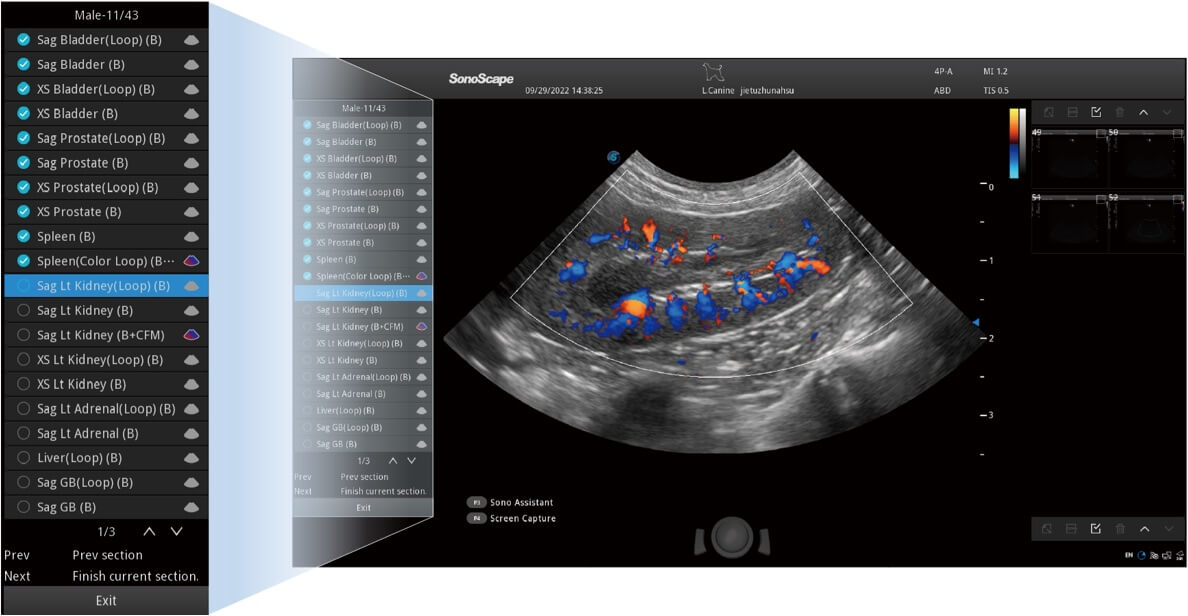

Przy pracach nad aparatem ProPet 60 uwzględniono najważniejsze preferencje i potrzeby weterynarzy, oferując finalnie przystępne cenowo i odpowiednio wyważone połączenie znakomitej precyzji klinicznej, zwiększonej wydajności i przemyślanego przebiegu pracy, niezastąpione w codziennej praktyce weterynaryjnej. Dzięki dostępowi do pełnej gamy głowic HD rozwiązanie to spełnia wszystkie potrzeby w zakresie obrazowania, umożliwiając wykonywanie badań jamy brzusznej, małych narządów, ortopedycznych, badań podczas rozrodu, a nawet badań serca i klatki piersiowej, a to wszystko przy doskonałym stosunku jakości do ceny.